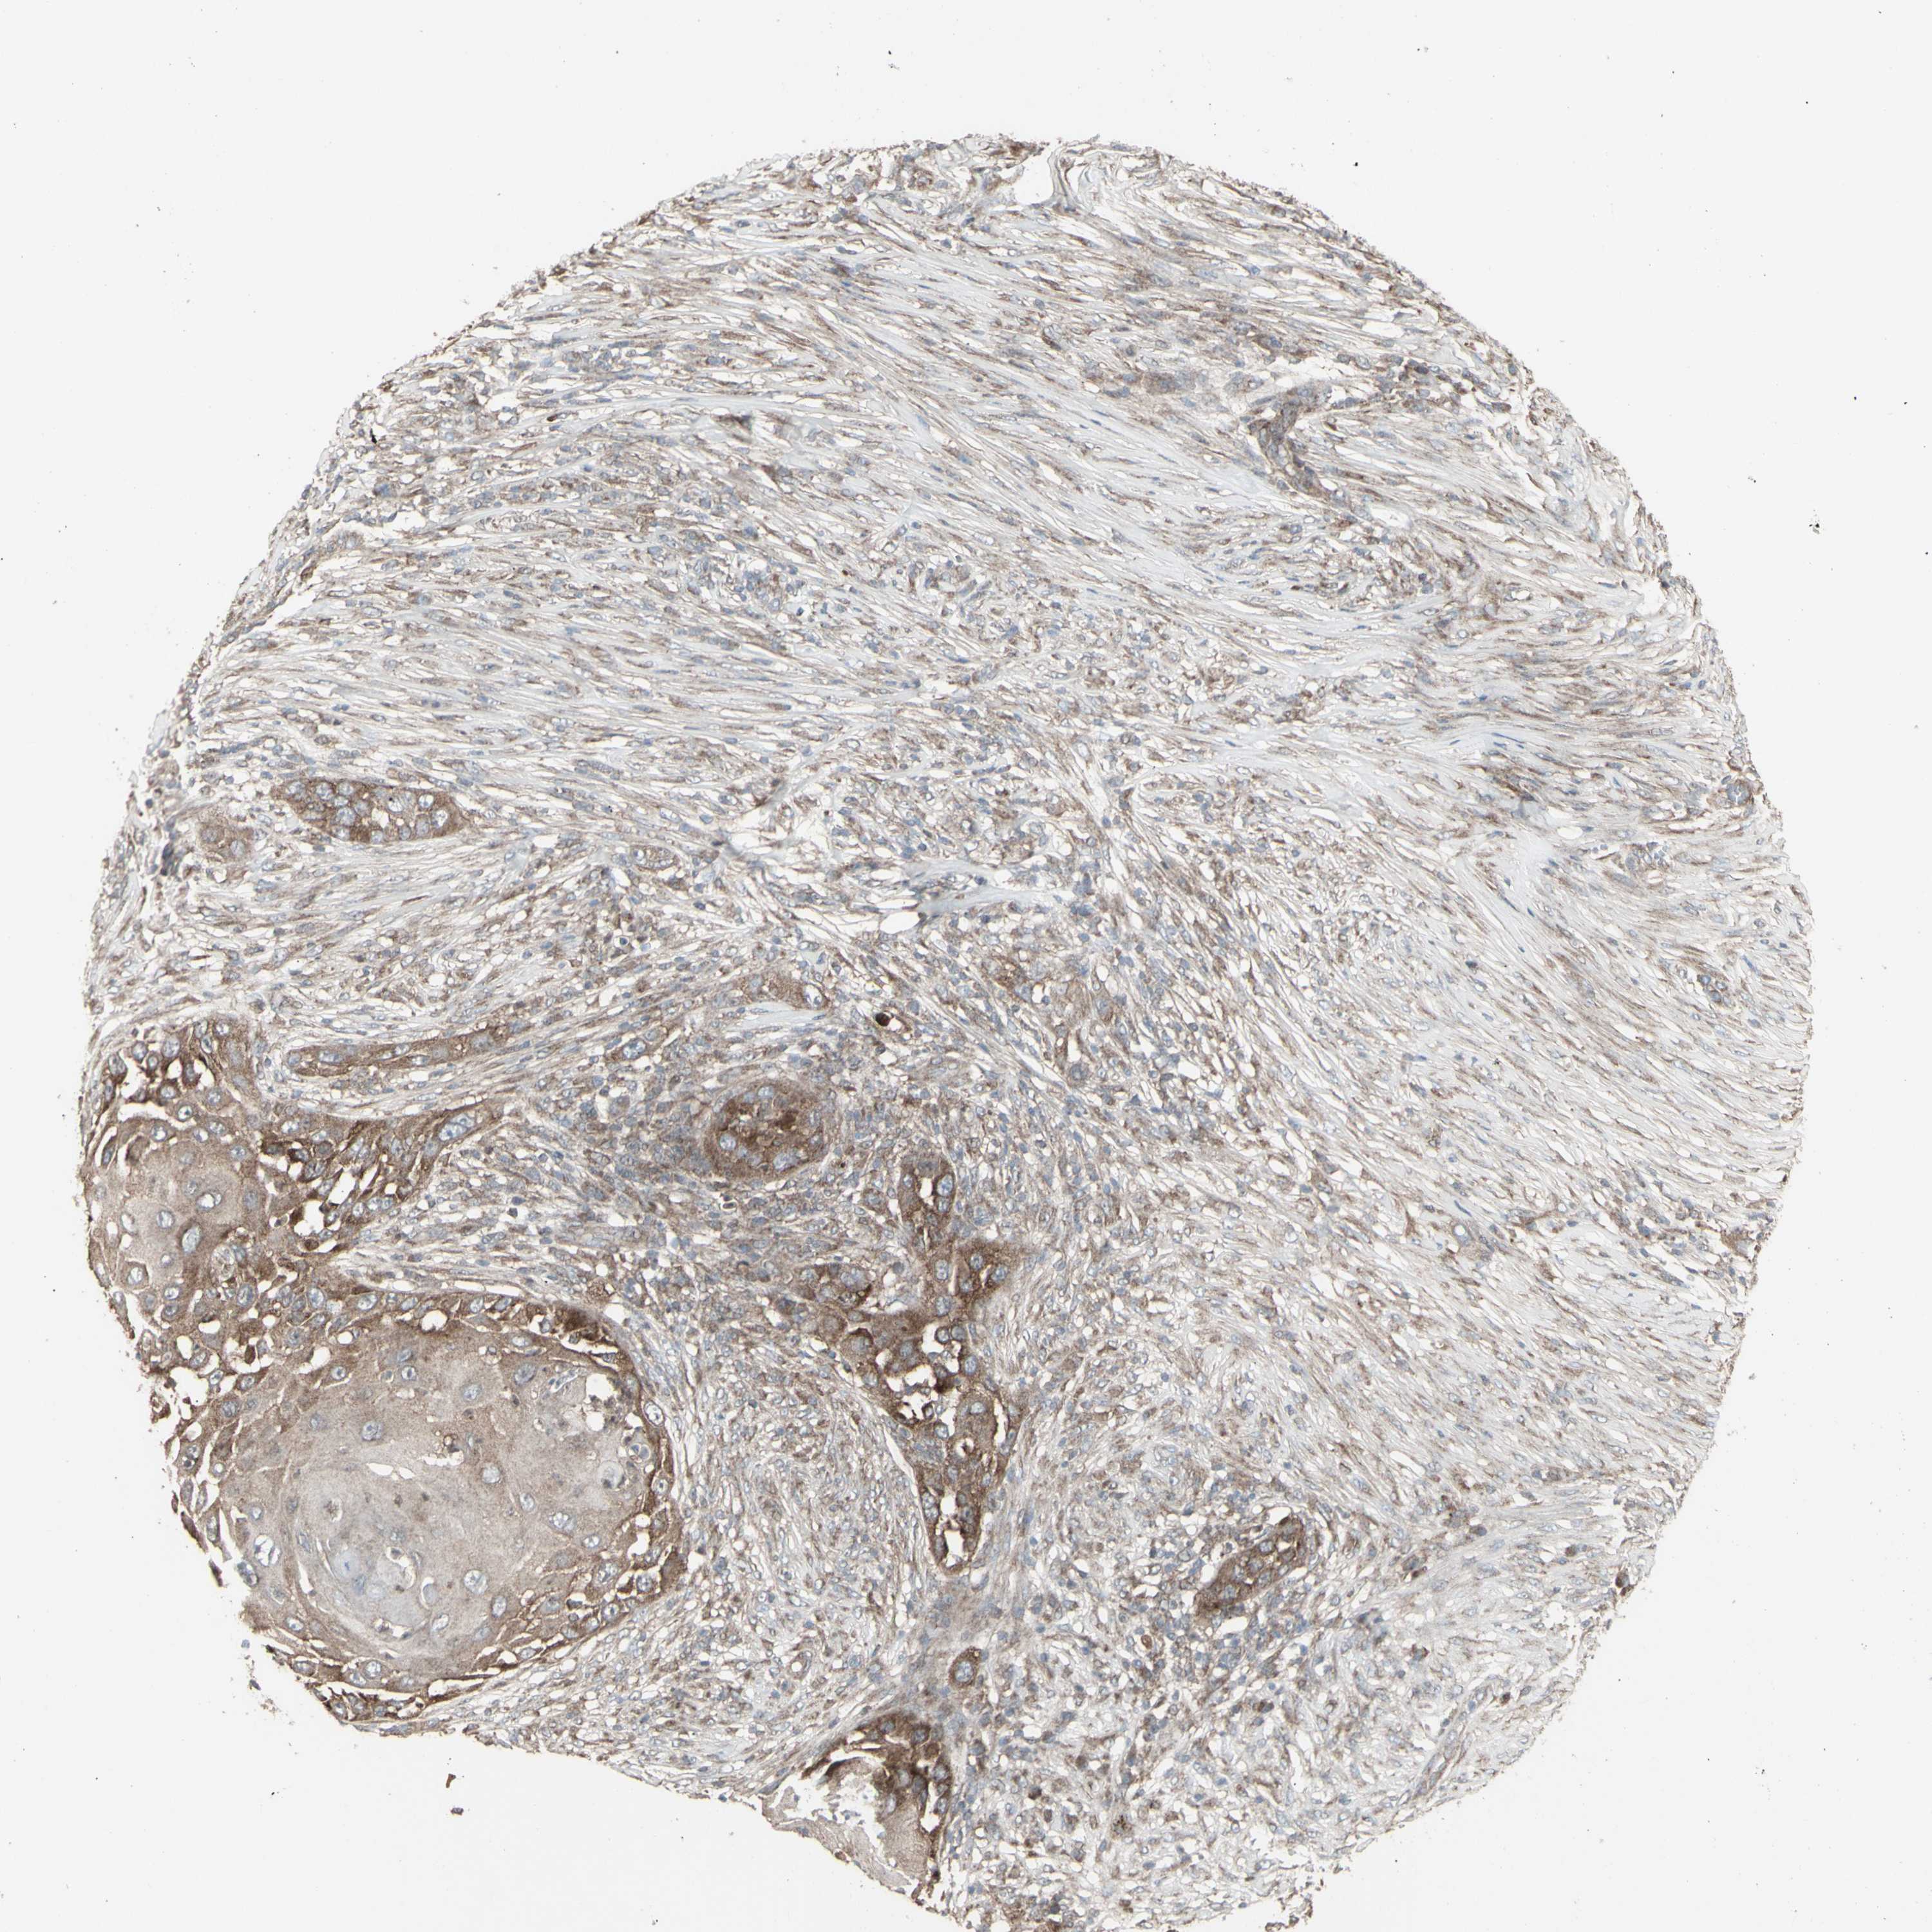

CANCER SKIN CANCER Show tissue menu

SKIN CANCER - Protein expressioni

A mouse-over function shows sample information and annotation data. Click on an image to view it in a full screen mode. Samples can be filtered based on level of antibody staining by selecting one or several of the following categories: high, medium, low and not detected. The assay and annotation is described here.

Each image is clickable and will lead to virtual microscopy that enables deeper exploration of all samples and also displays staining intensity scores, fraction scores and subcellular localization as well as patient and tissue information for each sample.

Antibody HPA046758

Basal cell carcinoma